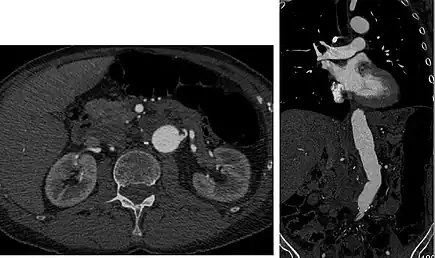

![]() Sagittal thin slice of a computed tomography angiography abdominal aortic aneurysm (AAA) (arrows) | |

Aorta and great arteries

CTA can be used in the chest and abdomen to identify aneurysms in the aorta or other major blood vessels. These areas of weakened blood vessel walls that bulge out can life-threatening if they rupture. CTA is the test of choice when assessing aneurysm before and after endovascular stenting due to the ability to detect calcium within the wall.[3] Another positive of CTA in abdominal aortic aneurysm assessment is that it allows for better estimation of blood vessel dilation and can better detect blood clots compared to standard angiography.[4]